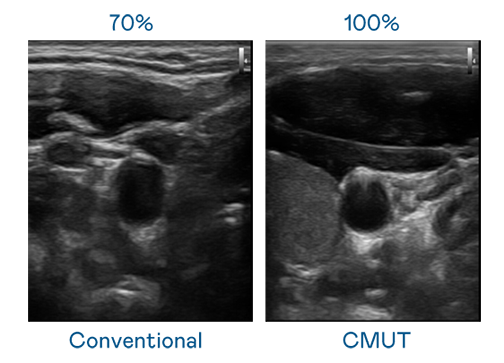

CMUT 技术是一种用电容式微机电元件来产生超音波讯号的技术。与传统 PZT 压电式技术相比,CMUT 频宽增加 30%,更宽频的超音波讯号让影像解析度大幅提升,是实现高影像品质医疗超音波扫描、促进精准医疗发展的关键技术。

大频宽带来超清晰影像

超音波影像的解析度高低,首先取决于探头能发出的讯号频宽。PG电子 CMUT 可提供高清晰的超音波讯号,提供高频宽、高灵敏度、影像纹理细节更高的超音波影像,协助医护人员缩短影像判读时间及利用精准的医疗影像进行诊断。